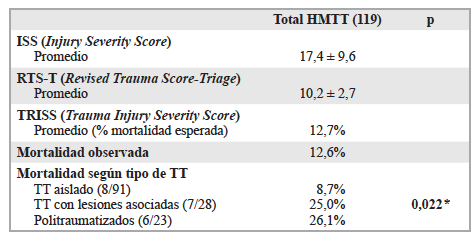

Julio César Núñez Villegas, Sergio Mauricio Rubel Cohen, Gabriel Alfredo Cavada Chacón, Laura Segovia González, Carlos Luis Matus Floody, Antonio Sa Cunha, Vilma Rodriguez, Rodrigo Abularach Cuellar

|

|

|